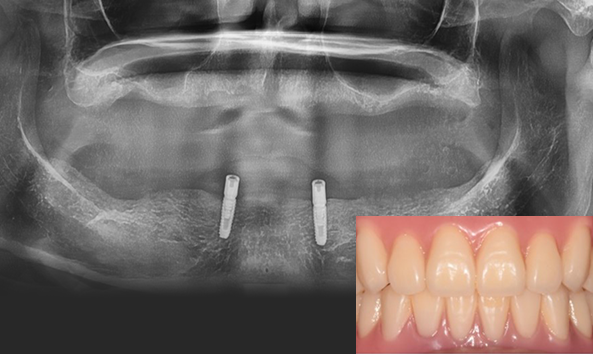

임플란트 틀니 선택의 기준

틀니를 오랫동안 사용하면 잇몸뼈가 지속적으로 흡수 되기 때문에 점점 헐거워지는

불편함을 겪을 수 있습니다. 또한 잇몸뼈가 줄어들게 되면

턱과 코의 주변 공간이 줄어들고 입술이 평평해지며 노화되어 보이기도 합니다. 틀니 사용이 어렵지만

전체 임플란트 수술과 비용이 부담스러운 경우 수술 시간, 통증, 비용이 훨씬 적은 임플란트 틀니를 권해드립니다.